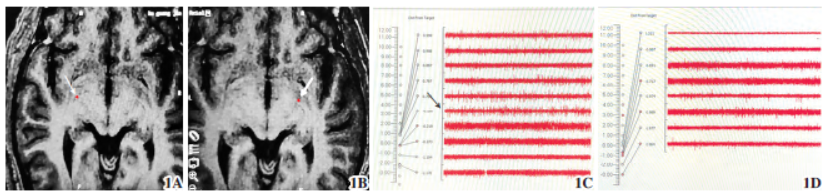

图1Gpi-DBS治疗痉挛性斜颈;1A术前左侧靶点轴位MRI定位;1B术前右侧靶点轴位MRI定位,箭头所指红点处;1C术中右侧Gpi电生理信号;1D术中左侧Gpi电生理信号,箭头为Gpi核团电信号,呈爆发性、不规则的高频放电;1E术后CT右侧电极与靶点融合;1F术后CT左侧电极与靶点融合

在典型电信号处分别置入(Medtronic3387-40)电极并安装临时体外刺激器。术后复查颅脑CT,与术前计划进行融合(图1),确认电极位置无偏移,观察无针道出血等严重并发症。术后即开启临时刺激器观察效果及不良反应,刺激参数设定为左侧Gpi:触点1-、2-、3+;右侧Gpi:触点8-、9-、10+;电压4.0V,频率180Hz,脉宽90μs。病人大部分症状较术前明显好转。但出现言语不清、构音障碍

本团队利用MRI冠状位层面找到视束,沿视束往后于双侧视束消失处上方3mm即靶点处。导航系统计算靶点坐标及设计手术入路,针道需避开脑沟、脑室及血管等结构。术中采用AlphaOmega电生理记录仪(以色列,Alphalab)记录核团电信号,采用对核团电信号影响较小的右美托咪定

麻醉及术中脑电双频指数(bispectral index,BIS)监测麻醉深度,病人术中唤醒后进行核团电信号描记。